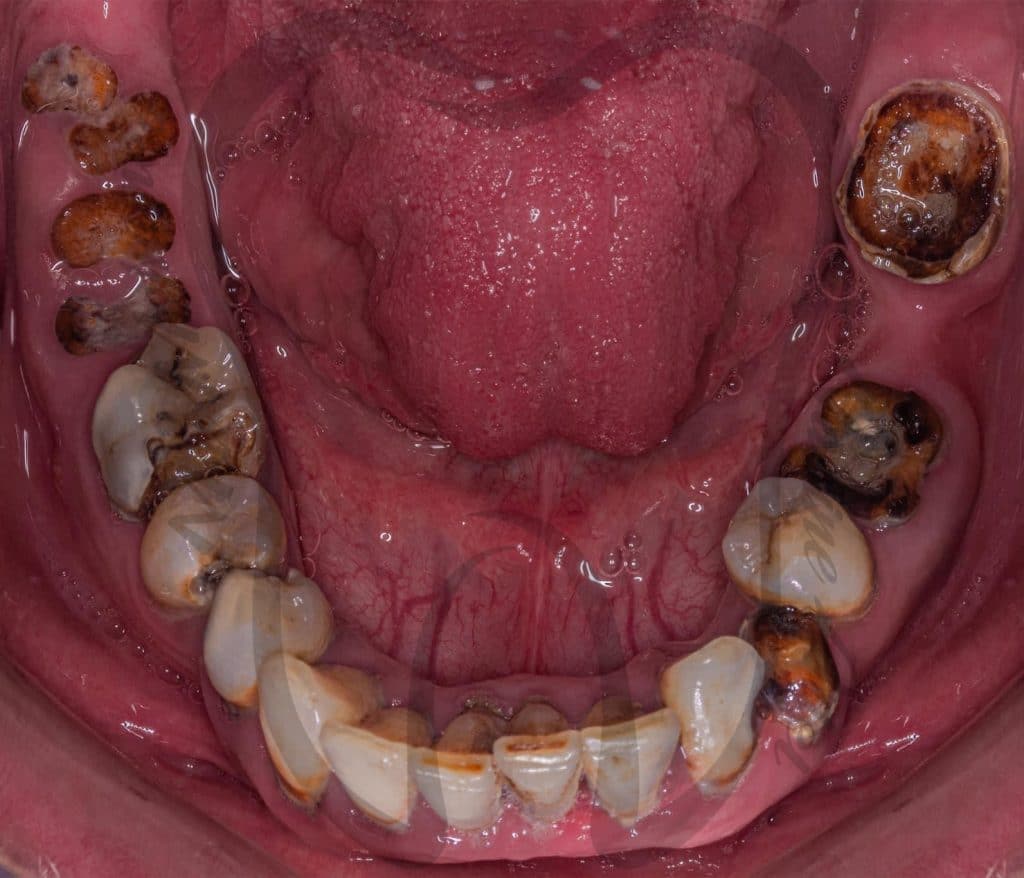

Our treatment plan included:

📌 10 Extractions

📌Full Mouth scaling and Root planing

📌 12 Endodontic treatment

📌 6 Post and Core

📌 Full Mouth Composite Restoration

📌 20 Unit Zirconium

📌 5 Unit PFM

📌 Lower Arch Class I Metallic RPD